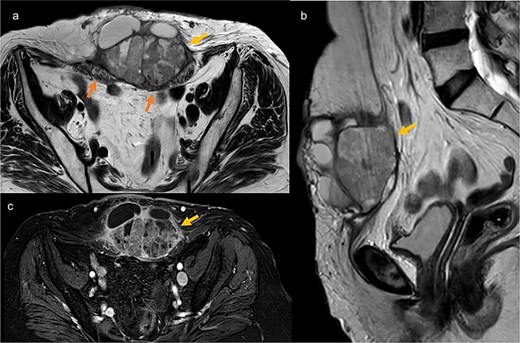

Eighteen months later, surveillance revealed a large mass of 12 cm at hypogastric trocar orifice, invading the skin with inflammatory signs (Fig. 1). The pelvic MRI revealed a heterogeneous lesion in the anterior abdominal wall, centered on the left rectus abdominis muscle, measuring 86 × 59 × 75 mm, suggestive of tumor recurrence (Fig. 2). PET scan showed a hypermetabolic pathological pelvic wall mass extending to the left side with a suspicious appearance. No other suspicious metabolic anomalies were detected in the visceral organs or bones. Ultrasound-guided biopsy revealed a moderately differentiated adenocarcinoma with an immunohistochemical profile compatible with endometrial origin.

Pelvic MRI in axial T2 (a), sagittal T2 (b), and axial T1 post-contrast (c), showing a well-defined mass at the trocar site, infiltrating the rectus abdominis muscles. The mass has regular contours, heterogeneous content with both fluid and tissue components, and exhibits enhancement after contrast injection.